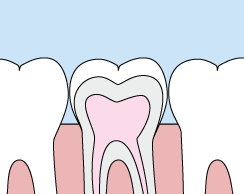

Crowns

crownsCrowns are a cosmetic restoration used to improve your tooth’s shape or to strengthen a tooth. Crowns are most often used for teeth that are broken, worn, or have portions destroyed by tooth decay.

A crown is a "cap" cemented onto an existing tooth that fully covers the portion of your tooth above the gum line. In effect, the crown becomes your tooth’s new outer surface. Crowns can be made of porcelain, metal, or both. Porcelain crowns are most often preferred because they mimic the translucency of natural teeth and are very strong.

Crowns or onlays (partial crowns) are needed when there is insufficient tooth strength remaining to hold a filling. Unlike fillings, which apply the restorative material directly into your mouth, a crown is fabricated away from your mouth. Your crown is created in a lab from your unique tooth impression, which allows a dental laboratory technician to examine all aspects of your bite and jaw movements. Your crown is then sculpted just for you so that your bite and jaw movements function normally once the crown is placed.